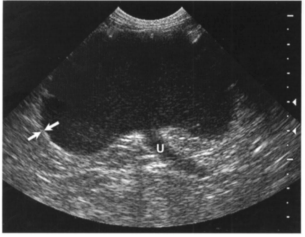

Рис 5. Обструктивный гидронефроз. Изображениеправой собаки с обструкцией мочеточника, вызванной конкрементом, продольная проекция. Обратите внимание на то, что дилатированные рецессусы (*) округлой формы и частично разделены гиперэхогенными перегородками, содержащими внутридольковые артерии и вены. Также визуализируется расширенная проксимальная часть мочеточника (U),сообщающаяся с лоханкой (Р)